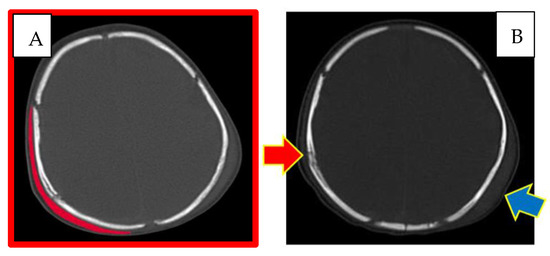

The newborn underwent a control brainstem and encephalic MRI on the same day. This investigation, in addition to confirming the presence of the right and left subgaleal haematomas already shown by the cranial CT scan, highlighted the presence of diffuse cerebral oedema, a right parietal subdural haematoma, subdural haematic effusion localised between the sickle and tentorium of the cerebellum, epidural haemorrhage at the posterior cerebellar site, intraparenchymal cortical haemorrhage at the left temporal site, frontobasal subarachnoid haemorrhage bilaterally, and hygromatous stratum at the left frontotemporal site.

Subsequent radiological investigations carried out during the infant’s stay in the ICU did not reveal any presence of vertebral and/or spinal cord lesions. On the contrary, they confirmed the evolution of the cranio-encephalic lesion complex, attesting to the appearance of diffuse ischaemic phenomena at the encephalic level, as discussed below.

In particular, it was hypothesised, considering the site and the different entities of the fractures present, the associated subgaleal haematomas, more present on the right, as well as the absence of ecchymotic skin lesions at the cranial level, patterned or not, that the compression was determined by the action of a hand positioned on the left parietal bone, thus coherent with the linear fracture highlighted by the instrumental investigations. The compression, according to the authors, would therefore have been exerted from the left parietal bone towards the right parietal bone, which was resting on a rigid surface, hence where the lesion complex was most evident and where a point of departure of the three radiating fractures, called the ‘point of impact’, could be clearly observed. This is also confirmed by the radiological appearance and extent of the subgaleal haematomas found bilaterally at the cranial level, which allows us to affirm the contemporaneity of the lesions, which were therefore determined by a single traumatic mechanism.